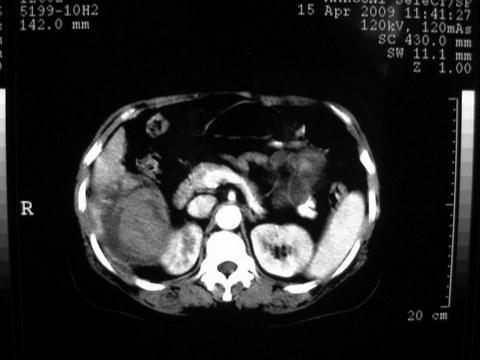

患者 女 51岁 两天前感觉上腹疼,无明显诱因,b超示肝右叶囊实性占位,边缘清楚,其内回声不均匀,ct增强如图,大家看看是什么 ,病人一年前及两月前b超检查只是提示胆囊炎

外院术后,证实肝癌合并出血

特点:1,病灶发展迅速,(2月前正常)[br] 2,囊实性,且并边界清晰光滑,呈右后叶赘生性。囊性区无强化,实性部分较多轻度强化,边界欠清。考虑囊腺癌或囊腺瘤。

出病理 中分化肝细胞癌合并出血